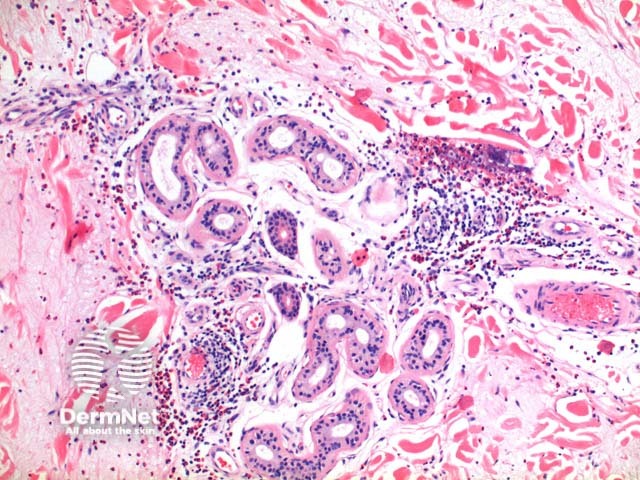

Scanning power view of Wells syndrome reveals a superficial and deep perivascular and interstitial inflammatory pattern (Figures 1 and 2). This can be seen to extend into the subcutaneous tissue (Figure 3) or even the underlying muscle. The inflammatory infiltrate is comprised of lymphocytes, histiocytes and abundant eosinophils (Figures 4,5 and 6). Degranulation of the eosinophils is seen forming flame figures (Figures 4 and 5). In this particular case extensive interstitial mucin is seen (Figures 4 and 5).

Figure 1

Figure 2